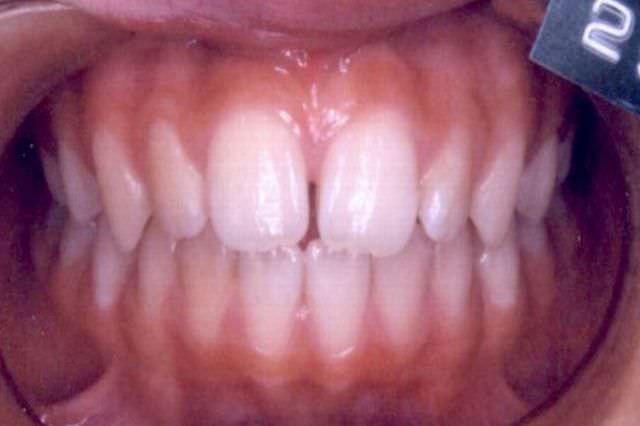

下顎前突 治療前

治療後

下顎前突 治療後

主訴 顎が出ていて見た目が気になる

診断名あるいは主な症状 下顎前突

年齢 11歳9ヶ月

治療に用いた主な装置 ブラケット装置 スタンダードエッジワイズ法

抜歯部位 非抜歯

治療期間 3年2ヶ月

治療費概算 70万+月々の調整料

リスク副作用 歯の根が吸収して短くなる場合があります。

歯茎が痩せて下がる場合があります。

舌で歯を押す唇を噛む等の癖が改善されない場合は、治療期間が長引く場合があります。

定期的に通院できない、キャンセルが多い場合は治療期間が長引きます。